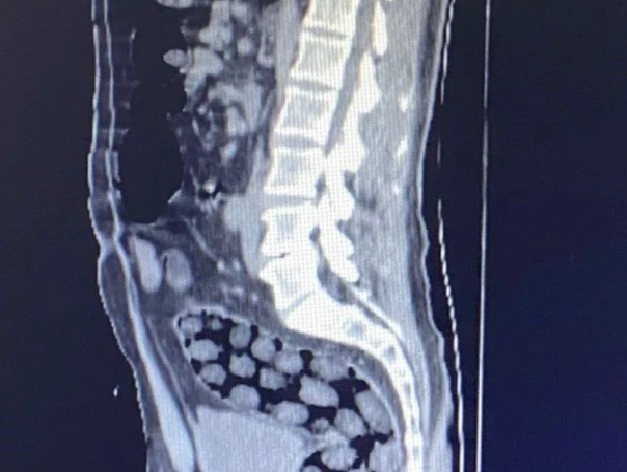

Bitlis’te mide ve bağırsaklarında toplam 91 paket uyuşturucu madde olduğu belirlenerek gözaltına alınan yabancı uyruklu 3 kişi, çıkarıldıkları adli mercilerce tutuklanarak cezaevine gönderildi.

Bitlis Valiliğinden yapılan açıklamada, uyuşturucu ile mücadele kapsamında elde edilen istihbari bilgiler doğrultusunda Tatvan’da durdurulan bir otobüste yabancı uyruklu 3 yolcunun yakalandığı belirtildi. Açıklamada, “Bitlis Emniyet Müdürlüğü Narkotik Suçlarla Mücadele Şube Müdürlüğü ve İstihbarat Şube Müdürlüğü ekiplerince gözaltına alınan ve Tatvan Devlet Hastanesine sevk edilen şüphelilerin röntgen ve tomografi görüntülerinde mide ile bağırsaklarında çok sayıda yabancı cisim bulunduğu tespit edilmiş, yapılan tıbbi müdahale ile şüphelilerin paketleyerek yuttuğu toplam 91 adet daralı ağırlığı 1 kilo 126 gram metamfetamin maddesine el konulmuştur. Şüpheliler, çıkarıldığı adli mercilerce tutuklanarak cezaevine gönderilmiştir. Hemşehrilerimizin huzuru ve güvenliği için uyuşturucu madde imalatı, kaçakçılığı ve kullanımına karşı yürütülen kararlı mücadelemiz devam edecektir” denildi.